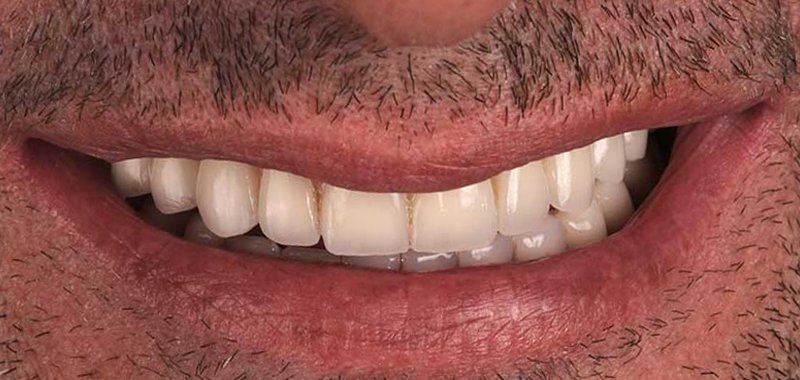

Gabino

Gabino llevaba tiempo insatisfecho con su sonrisa: tenía dientes ausentes y otros en mal estado, lo que afectaba su autoestima y bienestar. En nuestra clínica encontró la solución que buscaba: con tratamientos personalizados recuperó su sonrisa y mejoró su apariencia, ganando seguridad y confianza. Hoy disfruta de verse al espejo y mostrar al mundo una sonrisa atractiva y saludable.

Estas imágenes son testimonio de nuestro compromiso con la excelencia en la atención dental y la satisfacción del paciente. Cada sonrisa capturada aquí es el resultado de nuestro enfoque personalizado y de la utilización de las últimas tecnologías y técnicas en odontología.

Desde tratamientos de blanqueamiento dental hasta procedimientos de implantología con la tecnología X-Guide, cada paciente ha experimentado una mejora significativa en su salud dental y en su confianza en sí mismo. Pero más que palabras, creemos que una imagen vale más que mil palabras. Por eso, te invitamos a explorar estas fotos y a ver por ti mismo los resultados que puedes esperar cuando confías en la Clínica Dental Guitián.